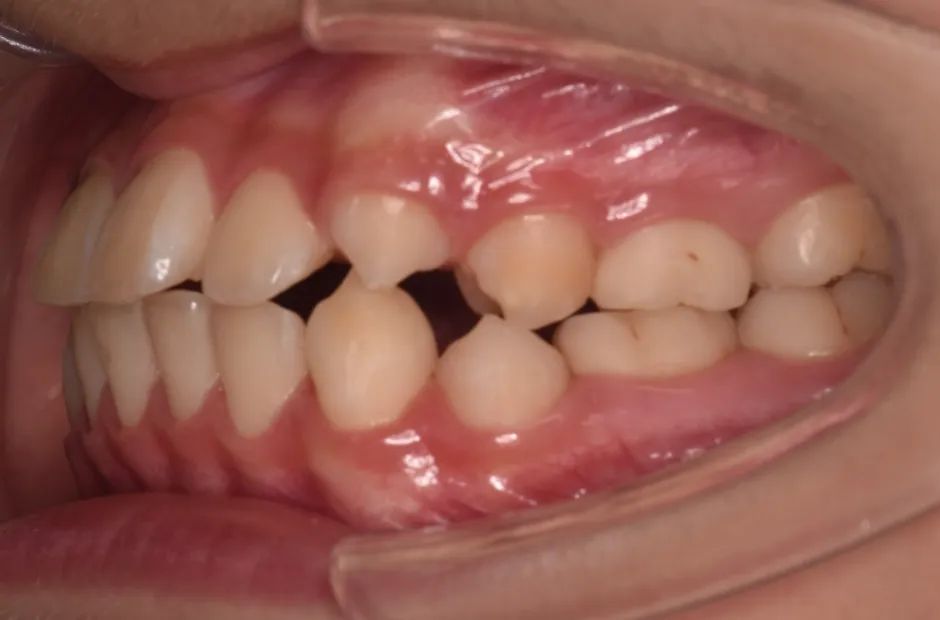

治療症例

ブラケット矯正

前歯部反対咬合

| 診断名・主訴 | 前歯部反対咬合 |

|---|---|

| 年齢・性別 | 14歳・男性 |

| 治療期間・回数 | 1年2か月 |

| 治療に用いた主な装置 | ブラケット矯正 |

| 抜歯部位 | なし |

| 治療費 | 60万円(税抜) |

| リスク・副作用 | 装置による違和感・疼痛・歯肉退縮・歯根吸収・虫歯のリスクなど |

治療前

治療中

治療後